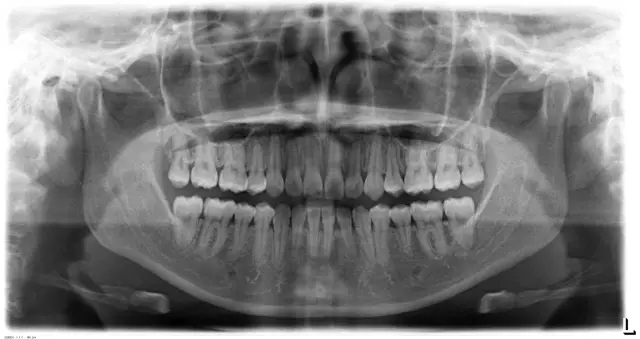

Damon 病例分享:安氏 II 類二分類露齦笑的矯治(董一磊)